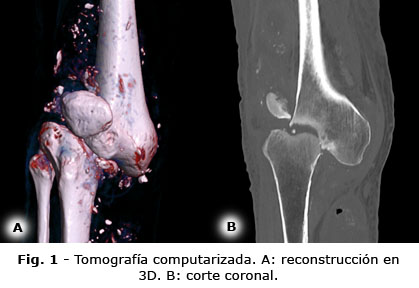

Se complementaron los estudios de imágenes con una tomografía computarizada y reconstrucción 3D (Fig. 1- Ver la imagen en alta definición) que mostró una fractura conminuta desplazada, del cóndilo femoral lateral, asociado a subluxación femorotibial, pérdida de la ubicación y morfología de la patela, irregularidades y esclerosis de los platillos tibiales y derrame articular heterogéneo con zonas de calcificación.

Por las características clínicas e imagenológicas, se consideró como diagnóstico una RC Eichenholtz-I (tabla 1) secundaria a una NA, por su enfermedad metabólica de base. Se realizaron intervenciones consistentes en inmovilización con férula de yeso, un plan de rehabilitación enfocado en mejorar la condición general, prevenir complicaciones y tratamiento del dolor con medicamentos gabapentinoides con ajuste de dosis, por las características mixtas de dolor y enfermedad renal de base.